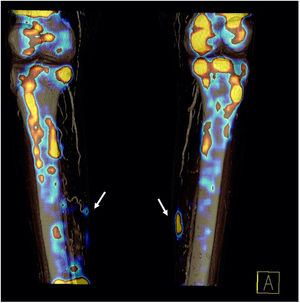

En el estudio planar con difosfonatos no se apreciaron hallazgos gammagráficos significativos en la fase vascular, mientras que, en la fase ósea, se observó una discreta captación del radiotrazador en regiones mediales de las piernas (fig. 1). Este hallazgo fue confirmado por la tomografía computarizada de emisión monofotónica (SPECT), tomografía computarizada de emisión monofotónica/tomografía computarizada (SPECT/TC) (fig. 2) e imagen de reconstrucción 3D (fig. 3), donde se evidenciaron depósitos focales del trazador en partes blandas, en relación con la localización de las lesiones ulcerosas más mediales, confirmando el diagnóstico de calcifilaxis.